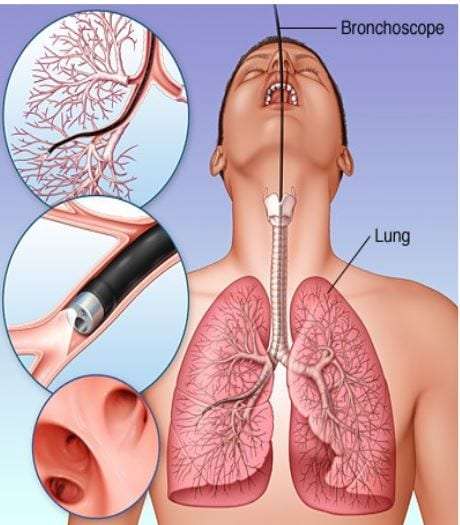

Здоровье дыхательной системы: бронхи и легкие